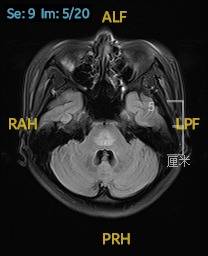

2023.02.09颅脑MR平扫示双侧基底节区及桥脑异常信号,考虑渗透性神经脱髓鞘综合征可能,脑桥部病灶较前范围增大,请结合临床,见图2。

图2 2023.02.09颅脑MR成像示双侧基底节区及桥脑见对称性片样长T1长T2信号,FLAIR呈高信号,较2023-01-18MR所示脑桥病灶范围增大。脑室、脑池、脑沟、脑裂未见明显异常。中线结构居中。